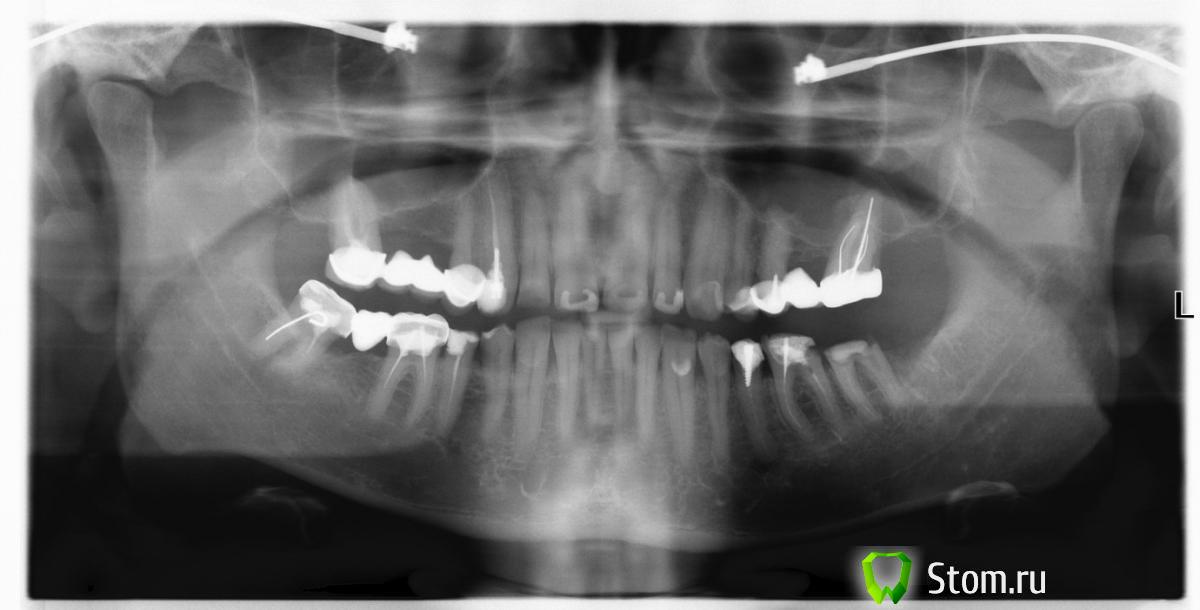

Salma Опубликовано 8 апреля, 2012 Поделиться Опубликовано 8 апреля, 2012 Все зубы под коронками,а также зубы 35,36,37и 45 нуждаются в перелечивании и новом протезированииС каждым зубом надо разбираться по отдельности,какие то прогнозы давать невозможно Ссылка на комментарий

Kostyets Опубликовано 8 апреля, 2012 Автор Поделиться Опубликовано 8 апреля, 2012 Спасибо, Salma. Врач рекомендует два крайних справа на нижней челюсти удалить и имплант. Чего не хочется. Там нет других вариантов? Ссылка на комментарий

Afffinity Опубликовано 8 апреля, 2012 Поделиться Опубликовано 8 апреля, 2012 Спасибо, Salma. Врач рекомендует два крайних справа на нижней челюсти удалить и имплант. Чего не хочется. Там нет других вариантов?Для начала пробовать перелечить. А потом уже думать о других вариантах Ссылка на комментарий

dok1 Опубликовано 8 апреля, 2012 Поделиться Опубликовано 8 апреля, 2012 Все зубы с вмешательством в каналы имеют разной степени недоработки."два крайних справа на нижней челюсти удалить" - попробуйте бором на прочность ткани зуба - если плотные и над десной, то сохраняйте и протезируйте. Ссылка на комментарий

samsonov Опубликовано 11 апреля, 2012 Поделиться Опубликовано 11 апреля, 2012 нижний седьмой слева я бы удалил. Ссылка на комментарий